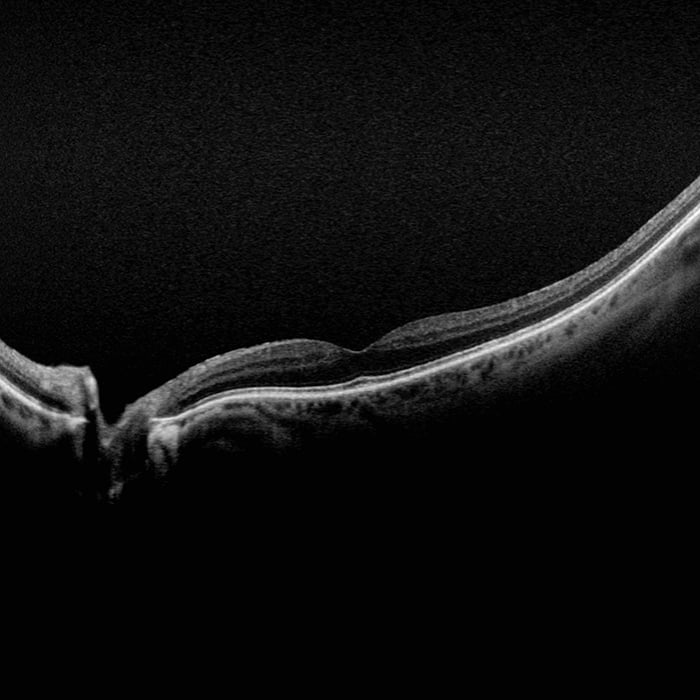

Spectral Domain Optical Coherence Tomography (OCT)

OCT Scan Types:

Line Scan

Raster Scan

Retina Topography Scan

Optic Nerve Head (ONH) Topography Scan

Retinal Nerve Fiber Layer (RNFL) Scan

Tomographic Imaging:

Signal Type: Optical scattering from tissue

Signal Source: Super luminescent Diode (SlD) 840 nm

Typical Axial Resolution: <7 micron (in tissue) Digital on-screen <5 micron

Transverse Resolution: <20 micron (in tissue), Digital on-screen <15 micron

Scan Depth: 2.3 mm (in tissue)

Spectral Domain OCT

A-Scan rate up to 70k cycles/s

Active eye tracking

Automatic scan positioning